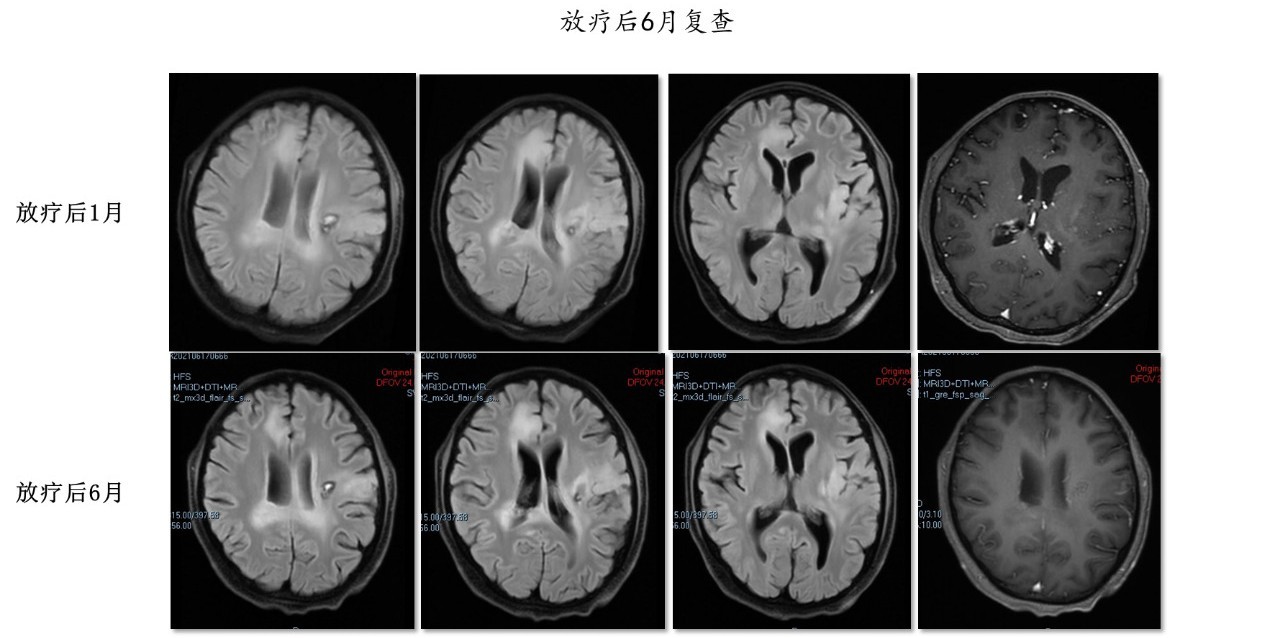

2021年3月9日开始行第一周期替莫唑胺联合TTFields治疗,化疗前复查头部MRI显示T2及增强病灶较前继续缩小。

2021年4月6日至今继续行替莫唑胺联合TTFields治疗,期间每2月复查一次MRI提示病灶稳定,未见进展。

患者为不可手术的多发胶质母细胞瘤,年轻,病情进展迅速,在明确病检后采取了TTFields同步放化疗的方案治疗后,迅速的控制了病情的发展,病灶在放疗的早期就出现了影像学上的响应,10次左右就出现了病灶的缩小,提示TTFields与放疗之间可能有协同作用。目前患者的PFS已经超过了6个月,一般情况良好,提示TTFields同步放化疗在非全切或无法手术的胶质母细胞瘤中安全有效。